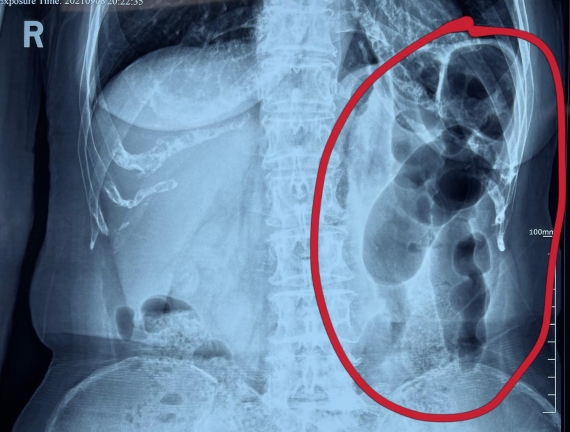

據(jù)省醫(yī)院消化病院消化二科姜子曄醫(yī)生介紹,韓大娘今年已經(jīng)73歲,家住哈爾濱市,一周前開始腹脹腹痛,有較為明顯的左側(cè)腹部疼痛,疼痛劇烈時會出現(xiàn)左側(cè)腹部鼓包情況,排氣排便后有所好轉(zhuǎn)。韓大娘家人見狀將其送到了黑龍江省醫(yī)院,門診檢查腹部平片提示為左側(cè)腹部積氣,口服全消化動力藥及通便治療后腹痛腹脹有所緩解,入院前再次突發(fā)左側(cè)腹痛加重伴有明顯腹脹,急診隨后以“腹痛腹脹原因待查”將韓大娘收入到消化病院消化二科。

姜子曄醫(yī)生熱情接待了韓大娘,為其進行了仔細(xì)查體,除了左側(cè)腹部壓痛并未見明顯異常,對癥給予灌腸后,韓大娘的腹脹有所緩解,第二天姜子曄醫(yī)生為韓女士進行了胃腸鏡檢查,也未見明顯異常。但此時韓大娘腹部平片結(jié)腸腸管擴張仍然很嚴(yán)重,腹痛腹痛也沒緩解,到底什么原因呢?消化二科主任陸以霞在查房時建議繼續(xù)給予韓大娘口服全消化動力藥,必要時灌腸治療,同時陸以霞主任在追問病史查體時發(fā)現(xiàn)韓大娘左下腹紅色皮疹和小水泡,反復(fù)抓撓腹部皮膚部分已結(jié)痂,高度懷疑為帶狀皰疹。